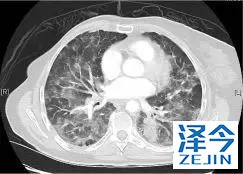

一位77岁的女性患有EPS15-NTRK1 IV期非小细胞肺癌,我们可以看到她的双肺满是病灶,并且出现了肝脏和脑转移,可以说是非常非常晚期了,

既往有乳腺癌史;

既往症状有厌食,乏力,咳嗽,高脂血症;

ECOG 1;

没有接受手术,放疗或化疗。

开始使用larotrectinib 100 mg BID并持续治疗,

第3周期开始:

肺靶病变达到缓解,我们可以明显的看到前后的图像,病灶明显缩小了,

脑转移病变显示缩小了95%!

初始, 2018年6月 3周期 2018年8月